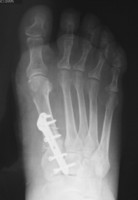

Basisosteotomie des 1. Mittelfußstrahles:

Dieses OP-Verfahren kommt bei größeren Abweichungen der Großzehe und bei einem IM-Winkel ab 15 Grad zur Anwendung. Durch diese Methode kann ein größeres Korrekturergebnis an der Großezehe erzielt werden, da das Köpfchen des 1. Mittelfußstrahles noch weiter zur Fußaußenseite hin verschoben werden kann. Der Knochenschnitt erfolgt hierbei an der Basis des 1. Mittelfußknochens und wird nach erfolgter Korrektur mittels einem Titanplättchen und 4 Schrauben  stabilisiert. Es handelt sich hierbei um sehr kleinvolumiges Material und kann in aller Regel belassen bleiben.

Auch hierbei erfolgt die Nachbehandlung mittels eines Vorfußentlastungsschuhs, welcher für insgesamt 4 Wochen nach der Operation getragen werden sollte. Wie auch bei dem oben genannten OP-Verfahren ist eine Vollbelastung mit diesem Spezialschuh ab dem 1. postoperativen Tag auch ohne Gehhilfen möglich.